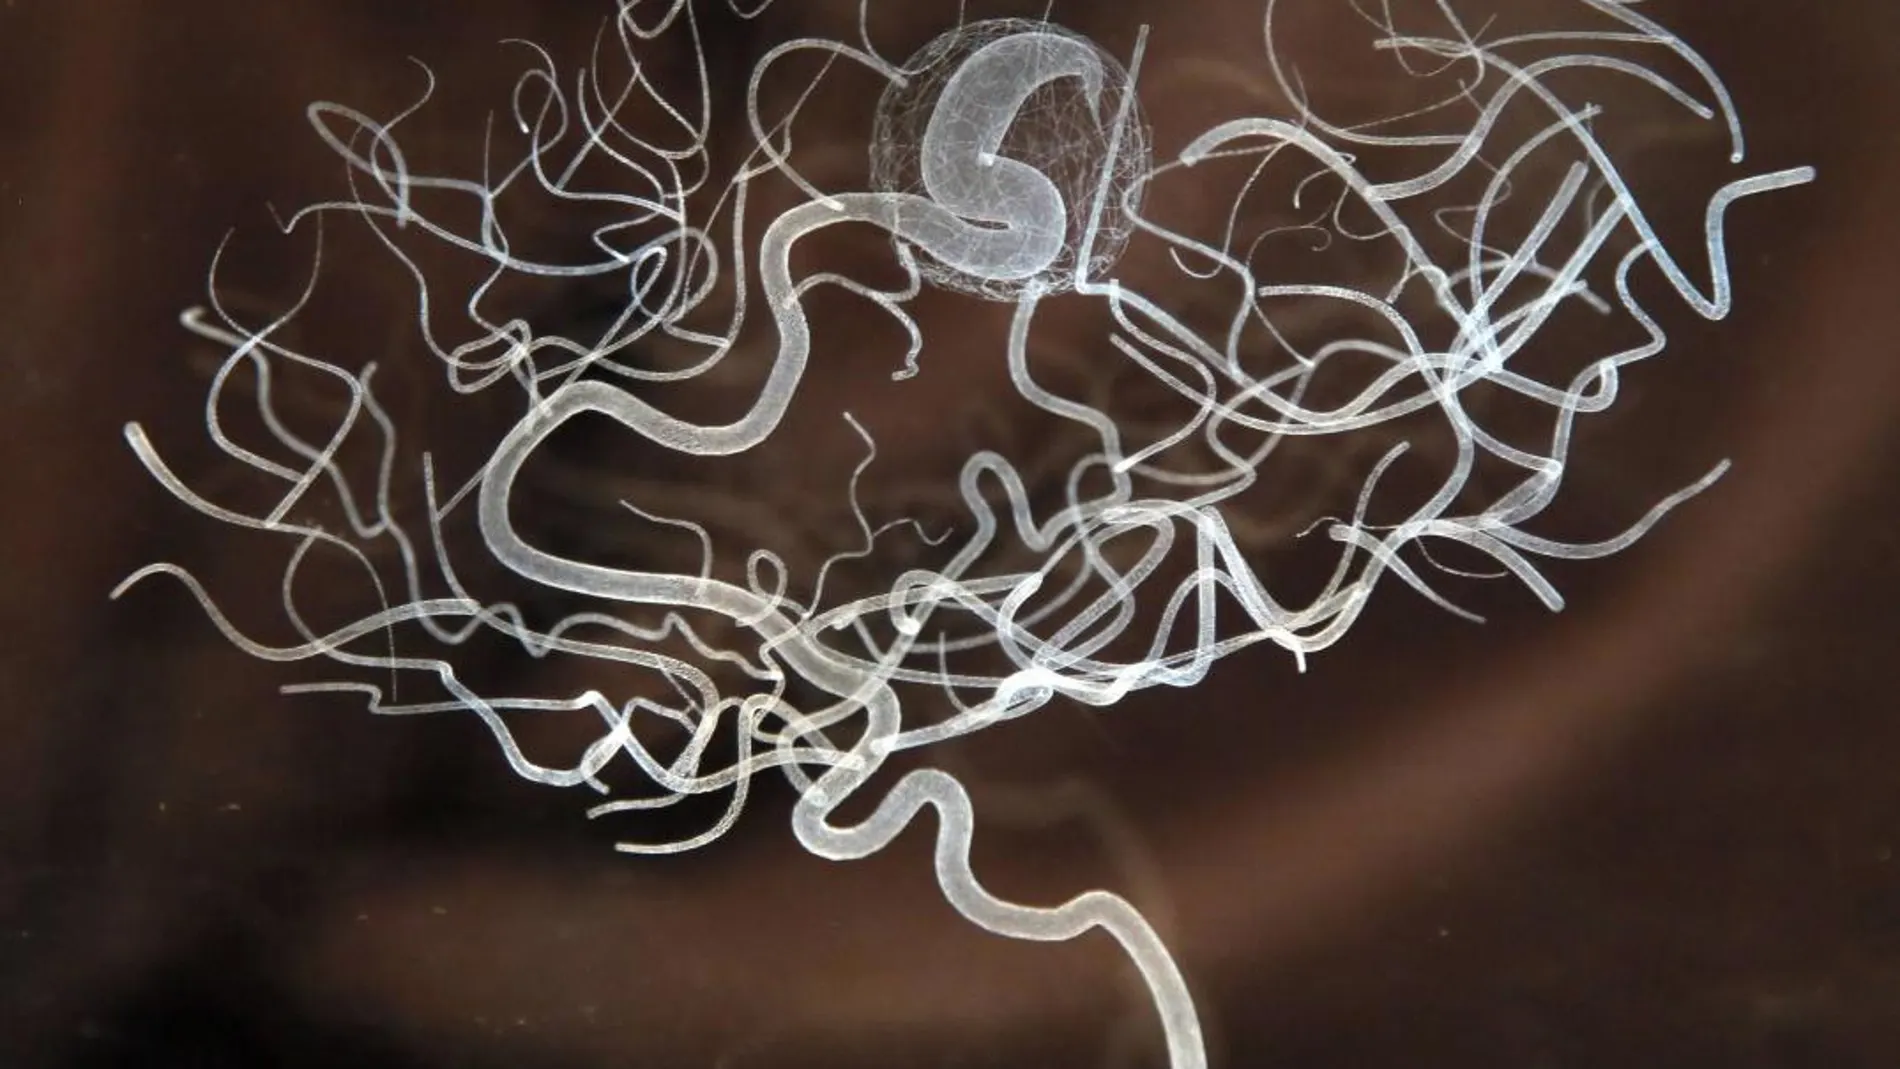

El análisis de grandes conjuntos de datos de muestras cerebrales post mortem de personas con y sin enfermedad de Alzheimer ha revelado nueva evidencia.

En concreto los autores han identificado cepas del virus del herpes humano 6A y 7 que se expresan de manera especialmente abundante en los cerebros de personas afectadas con el mal. De hecho este virus está presente en los cerebros dañados en cantidades hasta dos veces superiores que en los cerebros sanos.

Para llegar a tal conclusión, los autores analizaron datos de ADN y ARN de 622 cerebros donados para la investigación que padecían enfermedad y de otros 322 que eran sanos. Utilizando herramientas de gestión informática de grandes datos compararon cuidadosamente las trazas genéticas de cada uno de esos cerebros. En realidad no esperaban encontrar un virus específico en los tejidos. Realmente trabajaban en la búsqueda de algún patrón común que diera pistas sobre el origen del mal.

La sorpresa llegó al encontrar restos genéticos abundantísimos de virus del Herpes en los cerebros enfermos. «Ahora queremos desarrollar una prueba de sangre, suero sanguíneo o líquido cefalorraquídeo para detectar pacientes con alzhéimer o deterioro cognitivo leve con HHV-6 o HHV-7 activo. El objetivo es tratarles con antivirales con la esperanza de desacelerar su alteración cognitiva», señala uno de los autores.